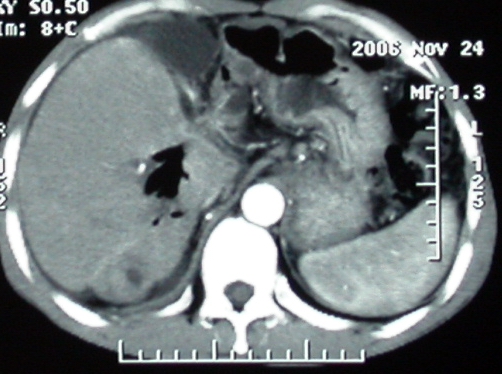

作者: rsyby 时间: 2006-11-28 22:53

增强ct所见

ct表现:1,胰腺钩突后方肿块,不均强化,中心密度低,钩突及门静脉前移。2:肝右后叶不均强化灶,突出肝表面,3:胆囊明显增大,肝内胆管及肝总管内积气。4:腹腔内少量积液。

考虑:1:胆囊炎,胆管炎。2:肝癌合并腹腔内转移灶,腹水。